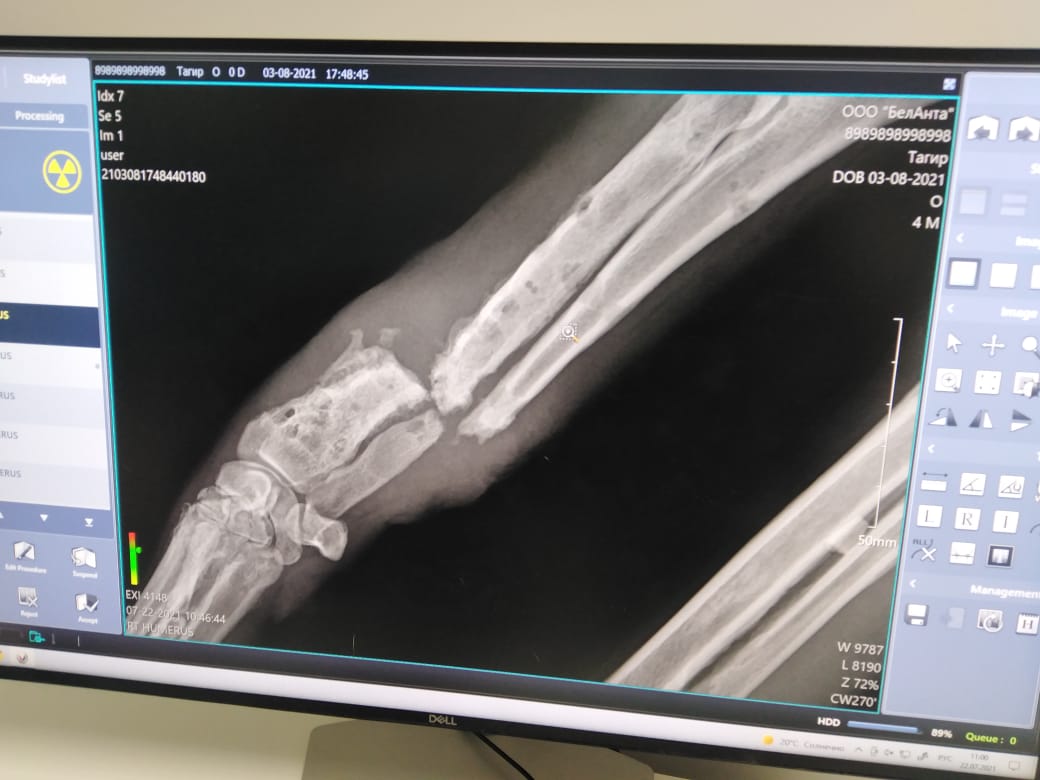

Ездили с ТАгиром на КТ лапки, ждем пластину и на операцию

Операция